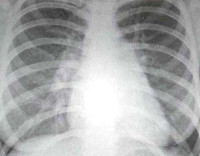

• Рентгенография грудной клетки. У большинства больных на рентгенограмме определяется кардиомегалия, выраженность которой зависит от стадии заболевания. Застой в малом круге кровообращения на фоне ХСН проявляется увеличением тени корней легкого и усилением легочного рисунка.